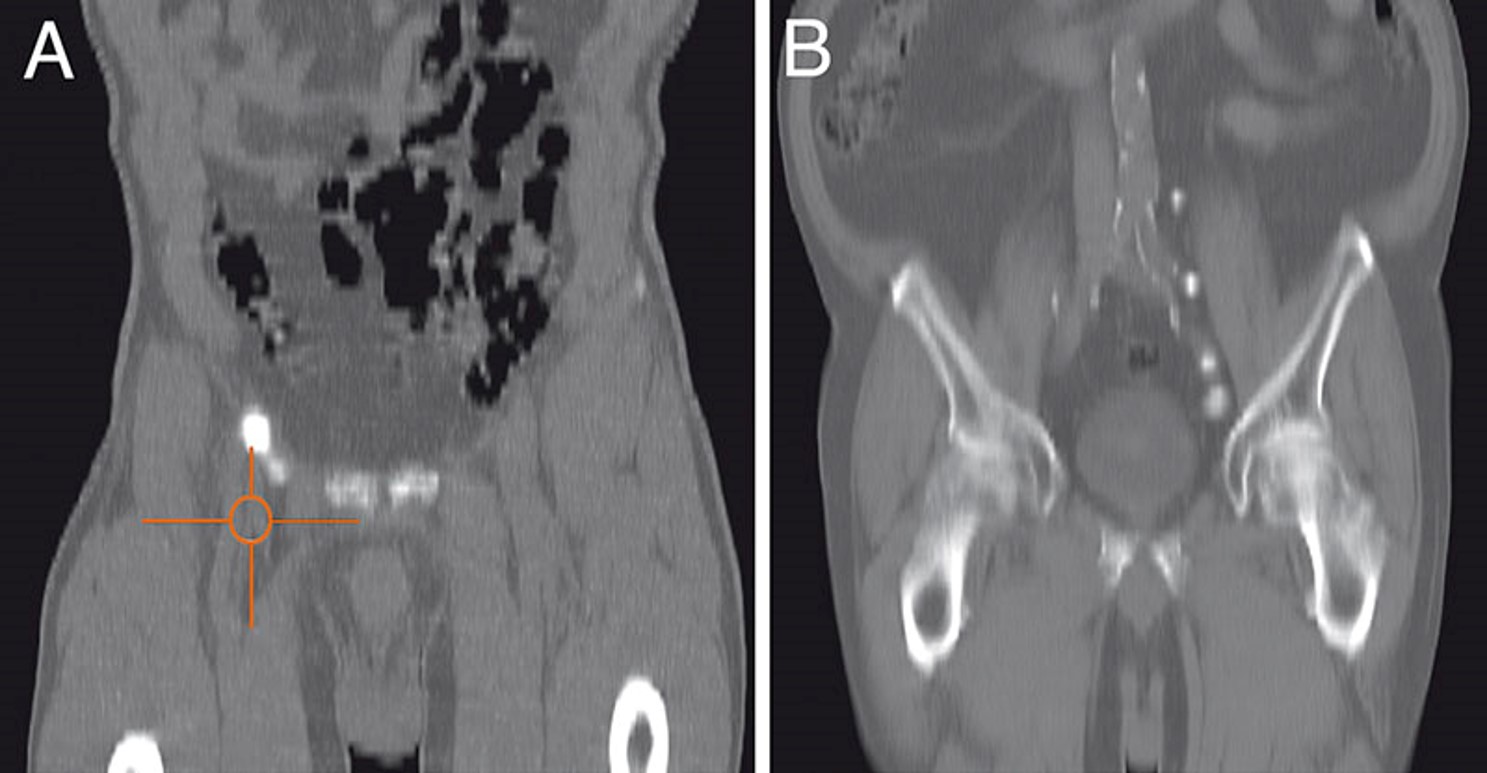

Τα πλεονεκτήματα της τροποποιημένης βουβωνικής λεμφαδενεκτομής είναι η ελάχιστη νοσηρότητα και ότι μπορεί να πραγματοποιηθεί χωρίς ιδιαίτερα τεχνικά μέσα. Η τεχνική περιεγράφηκε αρχικά από τον Catalona το 1988 και έχει υποστεί αρκετές τροποποιήσεις. Βασίζεται στην αρχή ότι οι φρουροί λεμφαδένες βρίσκονται πάντοτε στις άνω και στην κεντρική ζώνη του Daseler. Αυτό έχει τεκμηριωθεί και με μελέτες όπου χρησιμοποιήθηκε η τεχνική SPECT/CT. Πρακτικά αν δεν υπάρχουν διηθημένοι λεμφαδένες στην περιοχή που περικλείεται από την έσω επιφάνεια του μακρού προσαγωγού, την σαφηνή φλέβα και τον σπερματικό πόρο, τότε ο ασθενής είναι ελεύθερος μεταστατικής νόσου. Να σημειωθεί ότι οι εν τω βάθη λεμφαδένες άνωθεν της συμβολής της σαφηνούς με τη μηριαία και κάτωθεν του βουβωνικού συνδέσμου πρέπει να αφαιρεθούν.